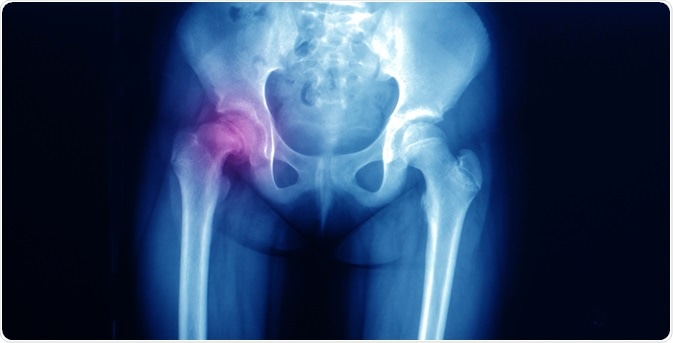

SCFEImage Credit: Yok_onepiece / Shutterstock.com

Biplanar X-rays are the primary study tool for this condition as they provide an accurate picture of the state of the bone. Supine anteroposterior and frog-leg lateral (Lauenstein) views are often requested to identify the pathology.

The pre-slip condition is signaled by a slight widening of the growth plate.

Early signs of slippage include joint capsule swelling, the presence of widening of the physis, and decalcification of the edge of the femoral shaft adjacent to the epiphysis.

A mild slippage is present when the femoral neck extends right up to the edge of the epiphysis.

The femoral head is displaced posteriorly with respect to the femoral neck.

The role of ultrasound is limited and shows the presence of a restricted effusion as well as displacement of the metaphysis before the slip occurs. MRI is also able to show the characteristic growth plate abnormalities before the epiphyseal slippage. CT scanning is indicated for the diagnosis of more complex deformities.